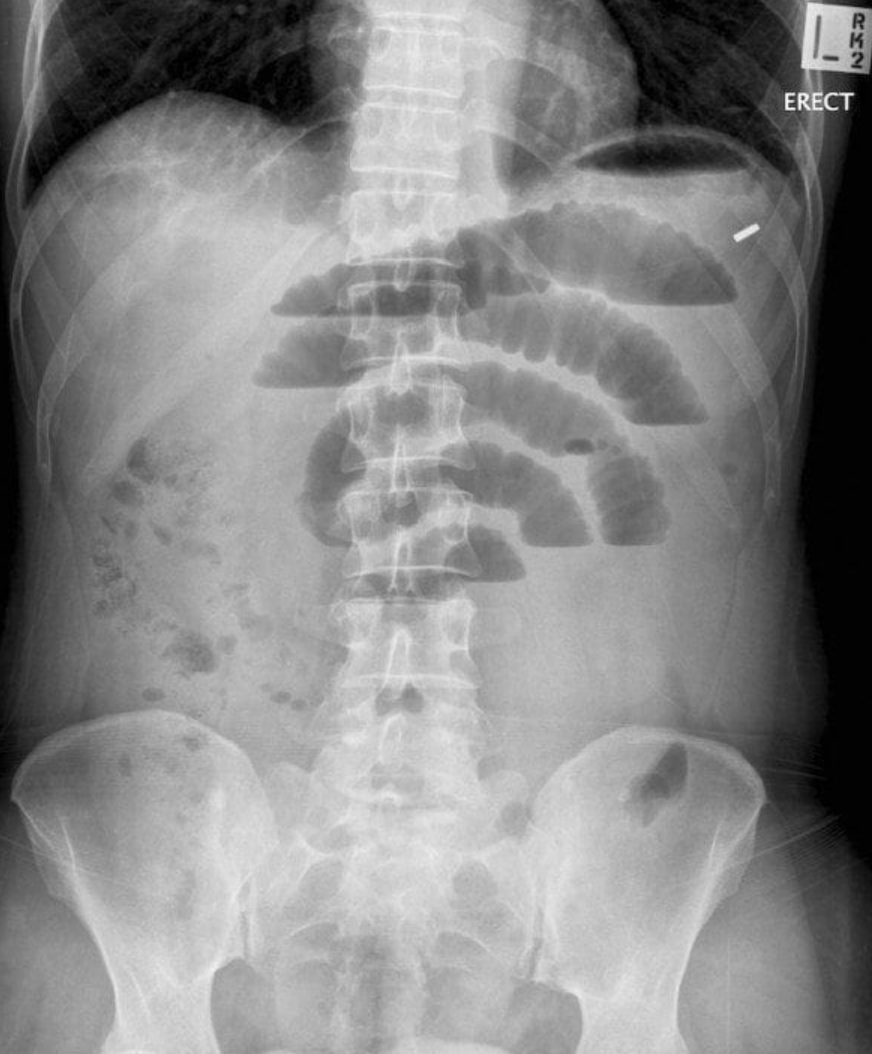

28세 여성이 3일 전부터 복통을 호소하며 병원을 찾았다. 환자는 4년 전에 담낭절제술을 받았으며, 현재 복부가 팽만하고 압통은 미약하다. 3일 동안 가스 배출이 없었다고 한다. 체온 37.3℃, 혈압 125/78 mmHg, 맥박수 90회/분, 호흡수 20회/분으로 측정되었다. 혈액검사 결과 Hb 13.8g/dL, WBC 8,200/mm3로 나타났다. 복부 X선 사진을 찍었다. 적절한 처치는 무엇인가?

• 복부 수술력이 있는 여성에서 복통, 복부 팽만, 압통이 있어 촬영한 X선에서 소장이 확장된 loop가 air-fluid level과 함께 보이고 있어 소장폐쇄를 의심할 수 있다. 우선적으로 코위관 삽입을 통해 장내 압력을 줄여주고, 수액을 투여하여 탈수를 교정한다.

• Small bowel obstruction(SBO)의 가장 흔한 원인은 post-operative adhesion다. 가스가 나오지 않는다는 점도 SBO를 강력하게 의심할 수 있는 소견이다.